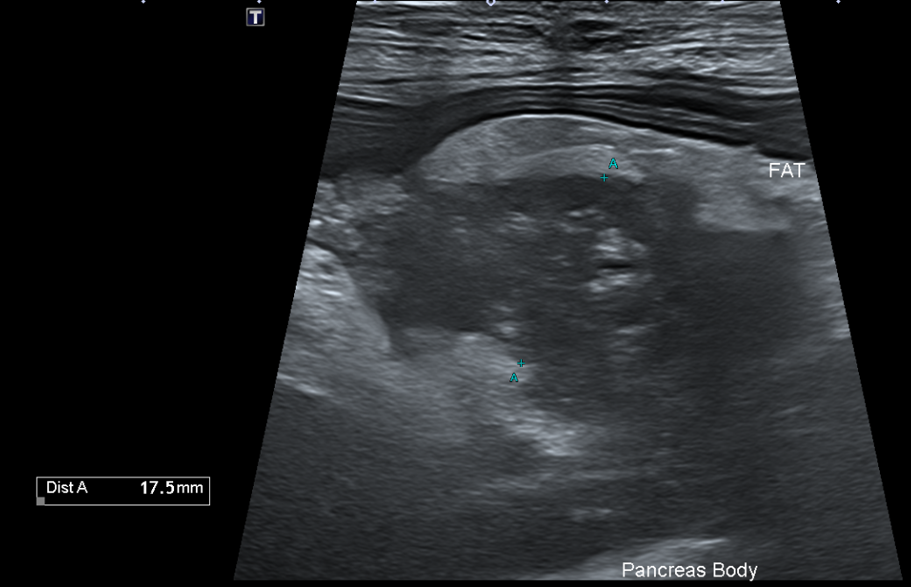

복부초음파

또한 복부 초음파상에서 뚜렷한 췌장 비후, 저에코성 음영, 주변 복막의 고에코성 소견 -> 확인되어 췌장염이 강력 의심되는 상황이었습니다.

Figure 2. 췌장 비후와 주변 복수 확인됨.

환자의 경우 뚜렷한 소화기 증상, 뚜렷한 염증 소견과 QPL 수치 상승, 복부초음파상 췌장염 비후, 복수 소견 확인되어 췌장염으로 진단되었습니다.

복부 초음파 검사

복부 초음파 검사는 췌장염 진단에 매우 유용한 검사입니다.- 췌장의 비대

- 췌장 주변 지방의 에코 변화